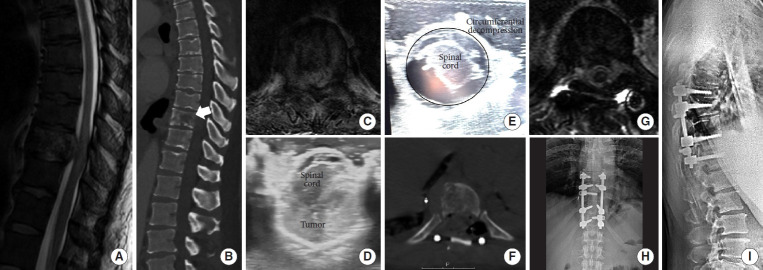

转移性脊柱疾病是一种日益增长的治疗挑战,需要在纳入新兴技术和尊重临床决策基本原则之间取得平衡。辅助治疗的进步,包括立体定向体放疗(SBRT)和化疗,显著提高了患者的长期生存率。手术决策应以完善的框架为指导,如NOMS(神经学、肿瘤学、机械、系统)标准、ESCC(硬膜外脊髓压迫)评分和SINS(脊柱不稳定肿瘤评分),以确保结构化和循证治疗方法。微创技术的整合,包括经皮内固定、消融技术和双门静脉内窥镜入路,降低了手术发病率,促进了更快的恢复。此外,碳纤维植入物通过更好地观察术后任何局部复发和更容易的放射计划,彻底改变了脊柱稳定。SBRT已成为一种关键的方式,提供精确的高剂量辐射,对脊髓的毒性最小,改善局部肿瘤控制和患者预后。多学科方法仍然是最重要的,需要脊柱外科医生、放射肿瘤学家和内科肿瘤学家之间的合作。在这篇叙述性综述中,我们旨在全面概述脊柱转移性肿瘤治疗的现状,重点是:(1)转移性脊柱护理的基础,(2)微创手术技术,(3)碳纤维螺钉的使用,(4)SBRT,(5)最大化患者安全的方法。

Metastatic spine disease represents a growing therapeutic challenge that demands a balance between incorporating emerging technologies while respecting the fundamental principles during clinical decision-making. Advances in adjuvant therapies, including stereotactic body radiotherapy (SBRT) and chemotherapy, have significantly improved long-term patient survival. Surgical decision-making should be guided by well-established frameworks such as the NOMS (neurologic, oncologic, mechanical, systemic) criteria, the ESCC (epidural spinal cord compression) scale, and the SINS (spinal instability neoplastic score), ensuring a structured and evidence-based approach to treatment. The integration of minimally invasive techniques, including percutaneous instrumentation, ablation techniques, and biportal endoscopic approaches, has reduced surgical morbidity and facilitated faster recovery. Additionally, carbon fiber implants are revolutionizing spinal stabilization by allowing better postoperative visualization of any local recurrence and easier radiation planning. SBRT has emerged as a critical modality, offering precise, high-dose radiation with minimal toxicity to the spinal cord, improving local tumor control and patient outcomes. A multidisciplinary approach remains paramount, requiring collaboration between spine surgeons, radiation oncologists, and medical oncologists. In this narrative review, we aim to provide a comprehensive overview of the current state of metastatic spine tumor management, focusing on: (1) fundamentals of metastatic spine care, (2) minimally invasive surgical techniques, (3) the use of carbon fiber screws, (4) SBRT, and (5) ways to maximize patient safety.